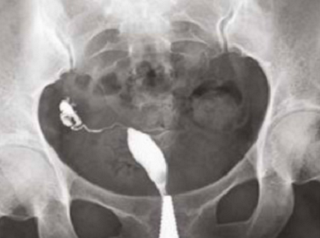

What does HSG assess?

Shape of the uterus

Normal shape

Unicornuate uterus

Complete septate uterus

Patency of fallopian tubes

Open tube

Closed tube

Uterine cavity

Clear/Normal

Submucosal fibroid

Adhesions/Synechiae